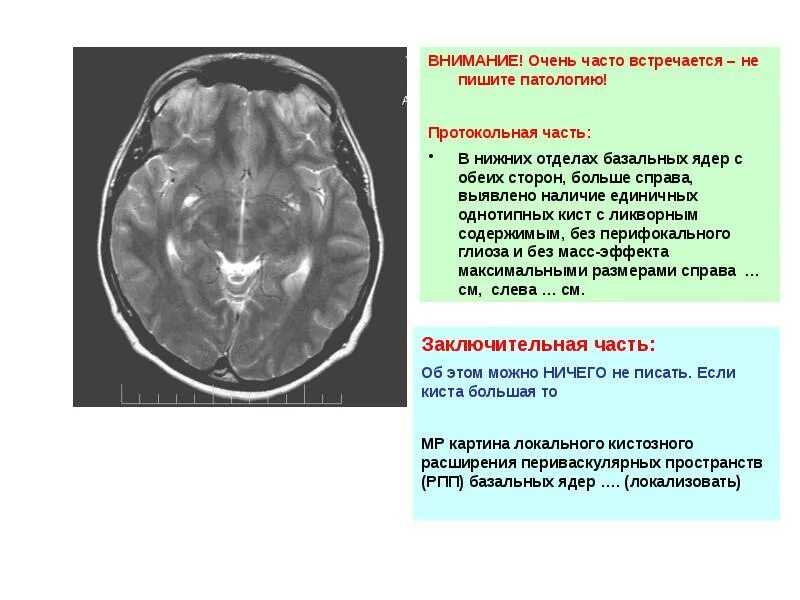

Киста базальных ядер слева